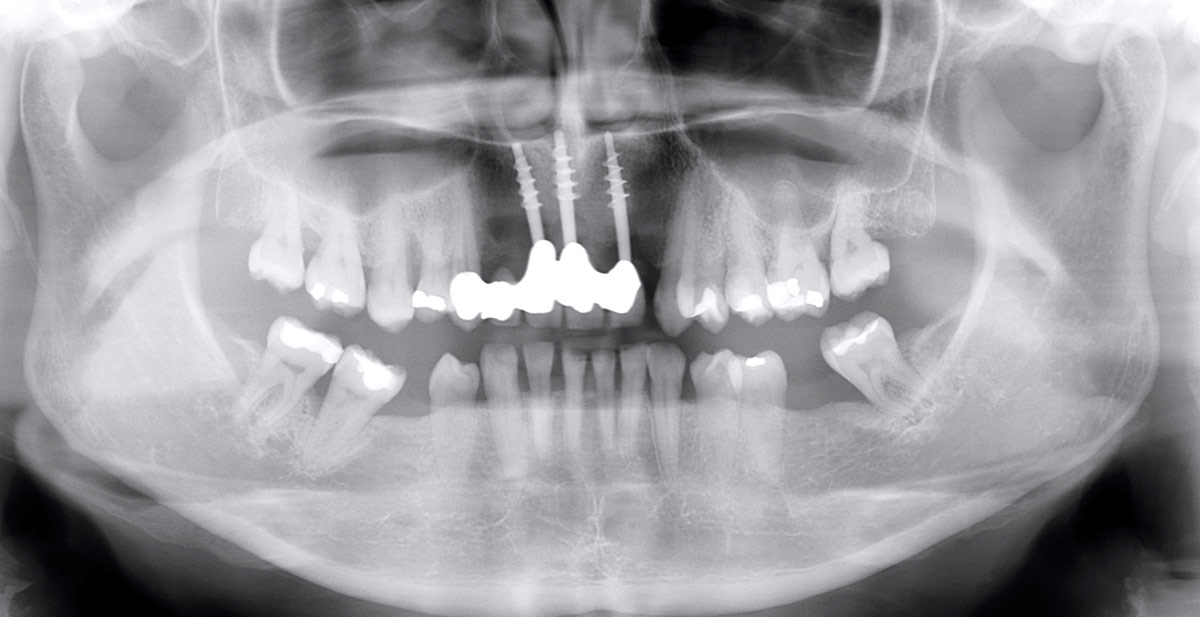

13/17 - X-ray scan after implant insertionRestoration of all four incisors with maxgraft® bonebuilder - Dr. Dr. Dr. O. Blume